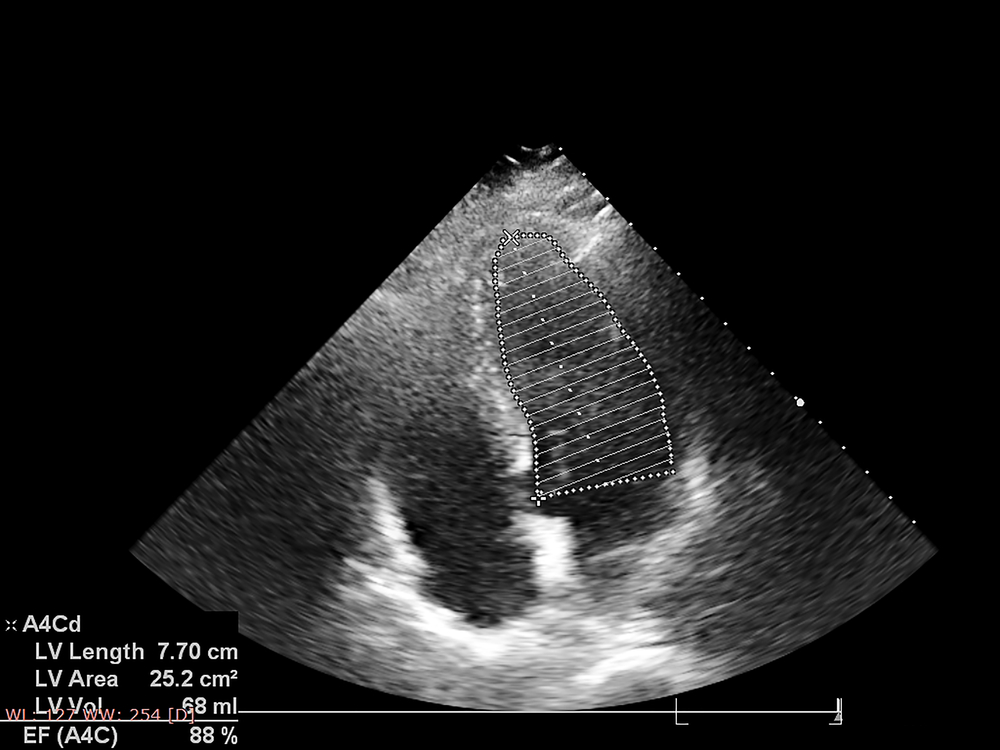

An echocardiogram is a type of non-invasive heart test that uses ultrasound imaging to produce pictures of your heart. It’s also called an echo or sonogram because it uses sound waves transmitted by a probe placed on your chest to create images in real time.